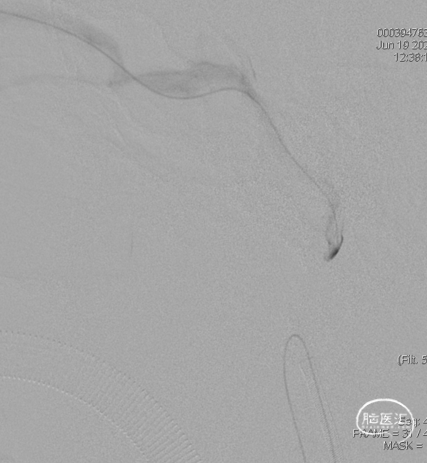

三枚弹簧圈对瘘口进行填塞,后通过Echelon微导管进行缓慢注胶,中途反复确认注胶形态。

术后造影见瘘口不显影。